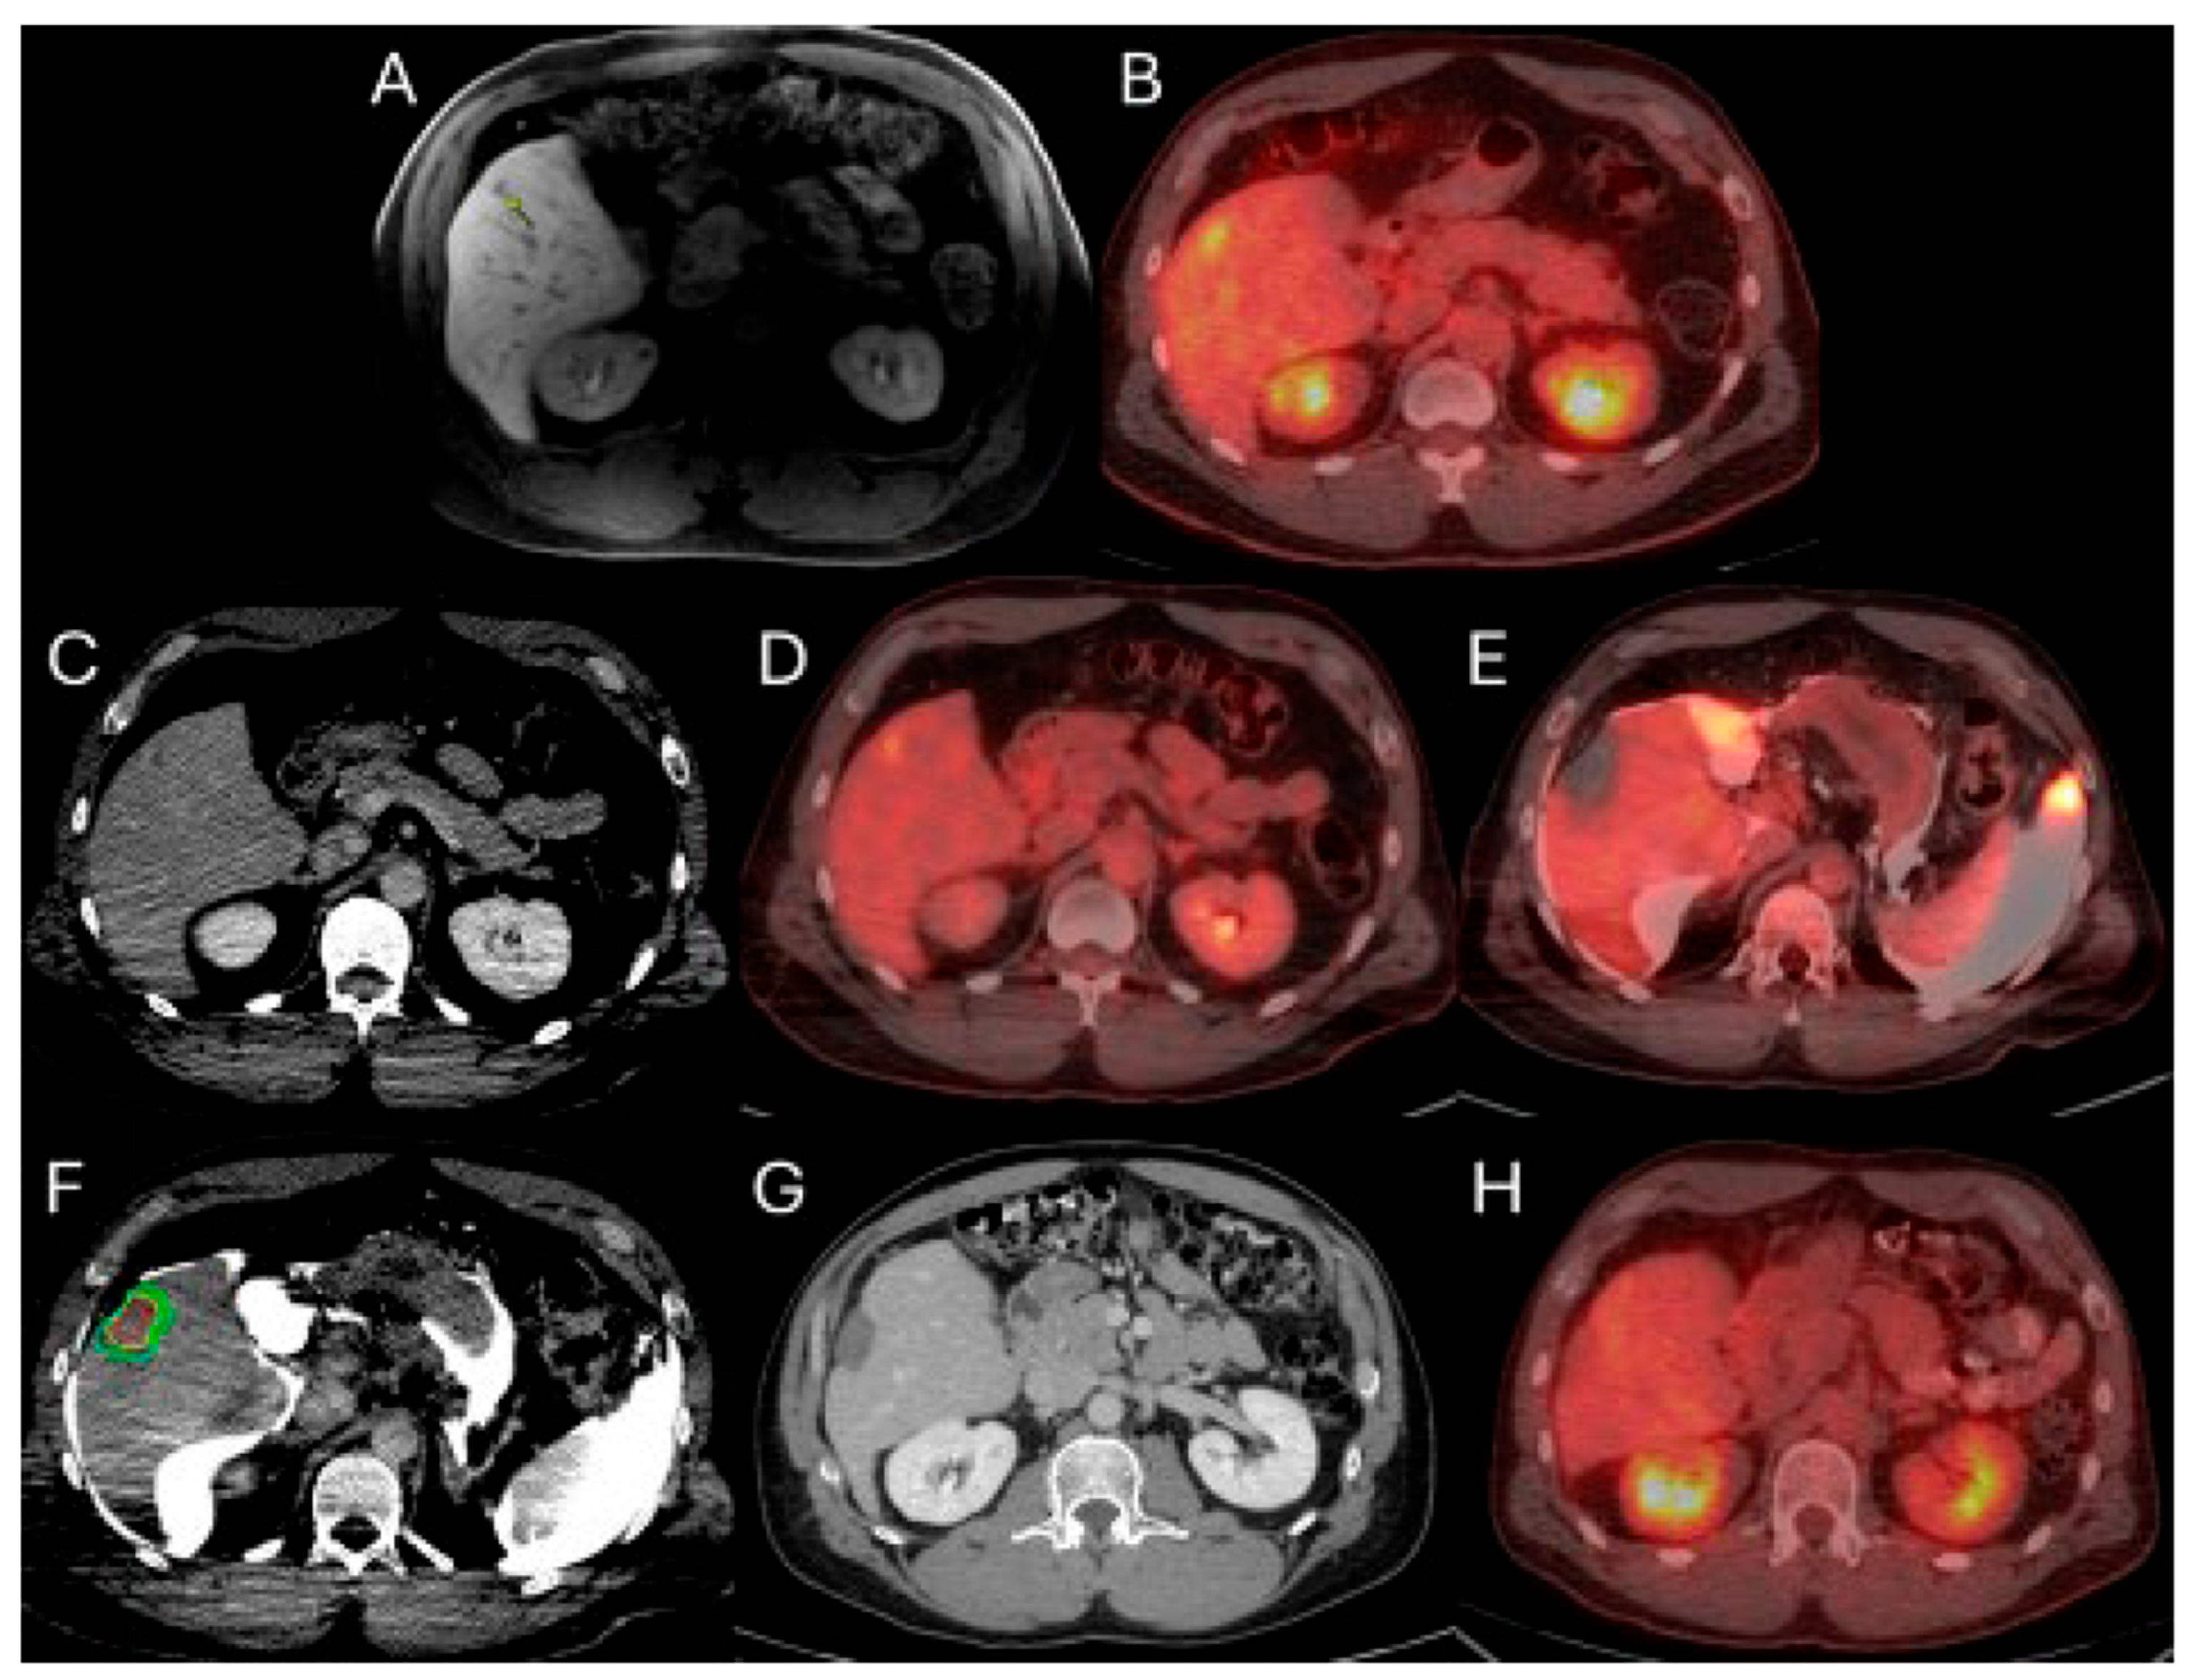

Figure 1.

56-year-old male with history of colorectal cancer under chemotherapy treatment presents with new segment 5 liver metastasis on T1 Magnetic Resonance Imaging with fat suppression (A) and fluorodeoxyglucose Positron Emission Tomography and Computer Tomography (FDG-PET/CT) (B) and undergoes microwave ablation (MWA). The target tumor is visible on the contrast enhanced Computer Tomography (ceCT) on ablation day imaging (C). Administration of the first FDG dose according to the split-dose PET/CT protocol (4 mCi), the FDG-avid tumor is clearly visualized (D). Hydrodissection is utilized to protect the adjacent ascending colon. After administration of the second FDG dose (8 mCi), the photopenic ablation zone indicates absence of residual metabolic activity (E). Ablation technical success is confirmed on post-ablation ceCT with utilization of MIM DEV software version 3.3.7. Red circle represents the tumor contours, yellow circle and green circle represent the 5 and 10 mm (mm) margins around the target tumor, respectively. The blue circle represents the contours of the ablation zone that uniformly covers the tumor with 5 mm margins, confirming technical success of thermal ablation (F). Follow-up anatomic and metabolic imaging at 2 years demonstrates involution of the ablation zone (G) with sustained local disease control (H).